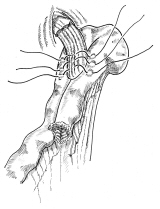

横隔膜切除後広背筋による再建

昔々、胸部外科の先生に頼まれて、描きました。